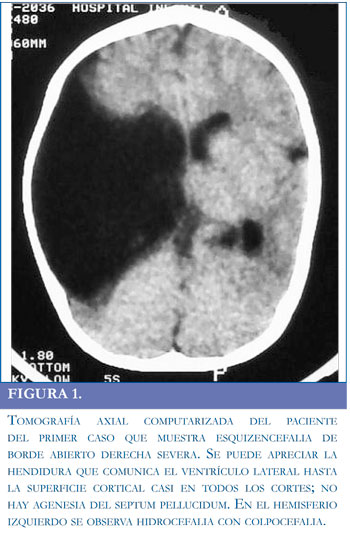

Paciente masculino de 6 años traído a consulta por retardo psicomotor global, con antecedentes de cierre prematuro de fontanelas, perímetro cefálico disminuido y aumento del tono muscular (manos cerradas permanentemente). Estos hallazgos motivaron la realización de una tomografía axial computarizada (TAC) que mostró esquizencefalia de labio abierto derecha (Figura 1). Se evidenció actividad paroxística epileptiforme derecha en un electroencefalograma realizado por presentar el paciente episodios compatibles con espasmo del sollozo.

Con respecto a los potenciales evocados somatosensoriales (Figura 3) es interesante mencionarque en el caso 2 no se encontró respuesta cortical (onda P37) en ninguno de los electrodos explorados (Cz, C3 y C4); por el contrario, en el caso 1 se halló una respuesta normal en el hemisferio cerebral conservado (electrodo C3) y no hubo respuesta en el lado de la lesión (electrodo C4). La ausencia de la respuesta refleja probablemente la ausencia del tejido encefálico encargado del procesamiento cortical del estímulo somatosensorial. Por tanto, los resultados de los potenciales somatosensoriales son coherentes con el cuadro clínico y con las imágenes cerebrales.